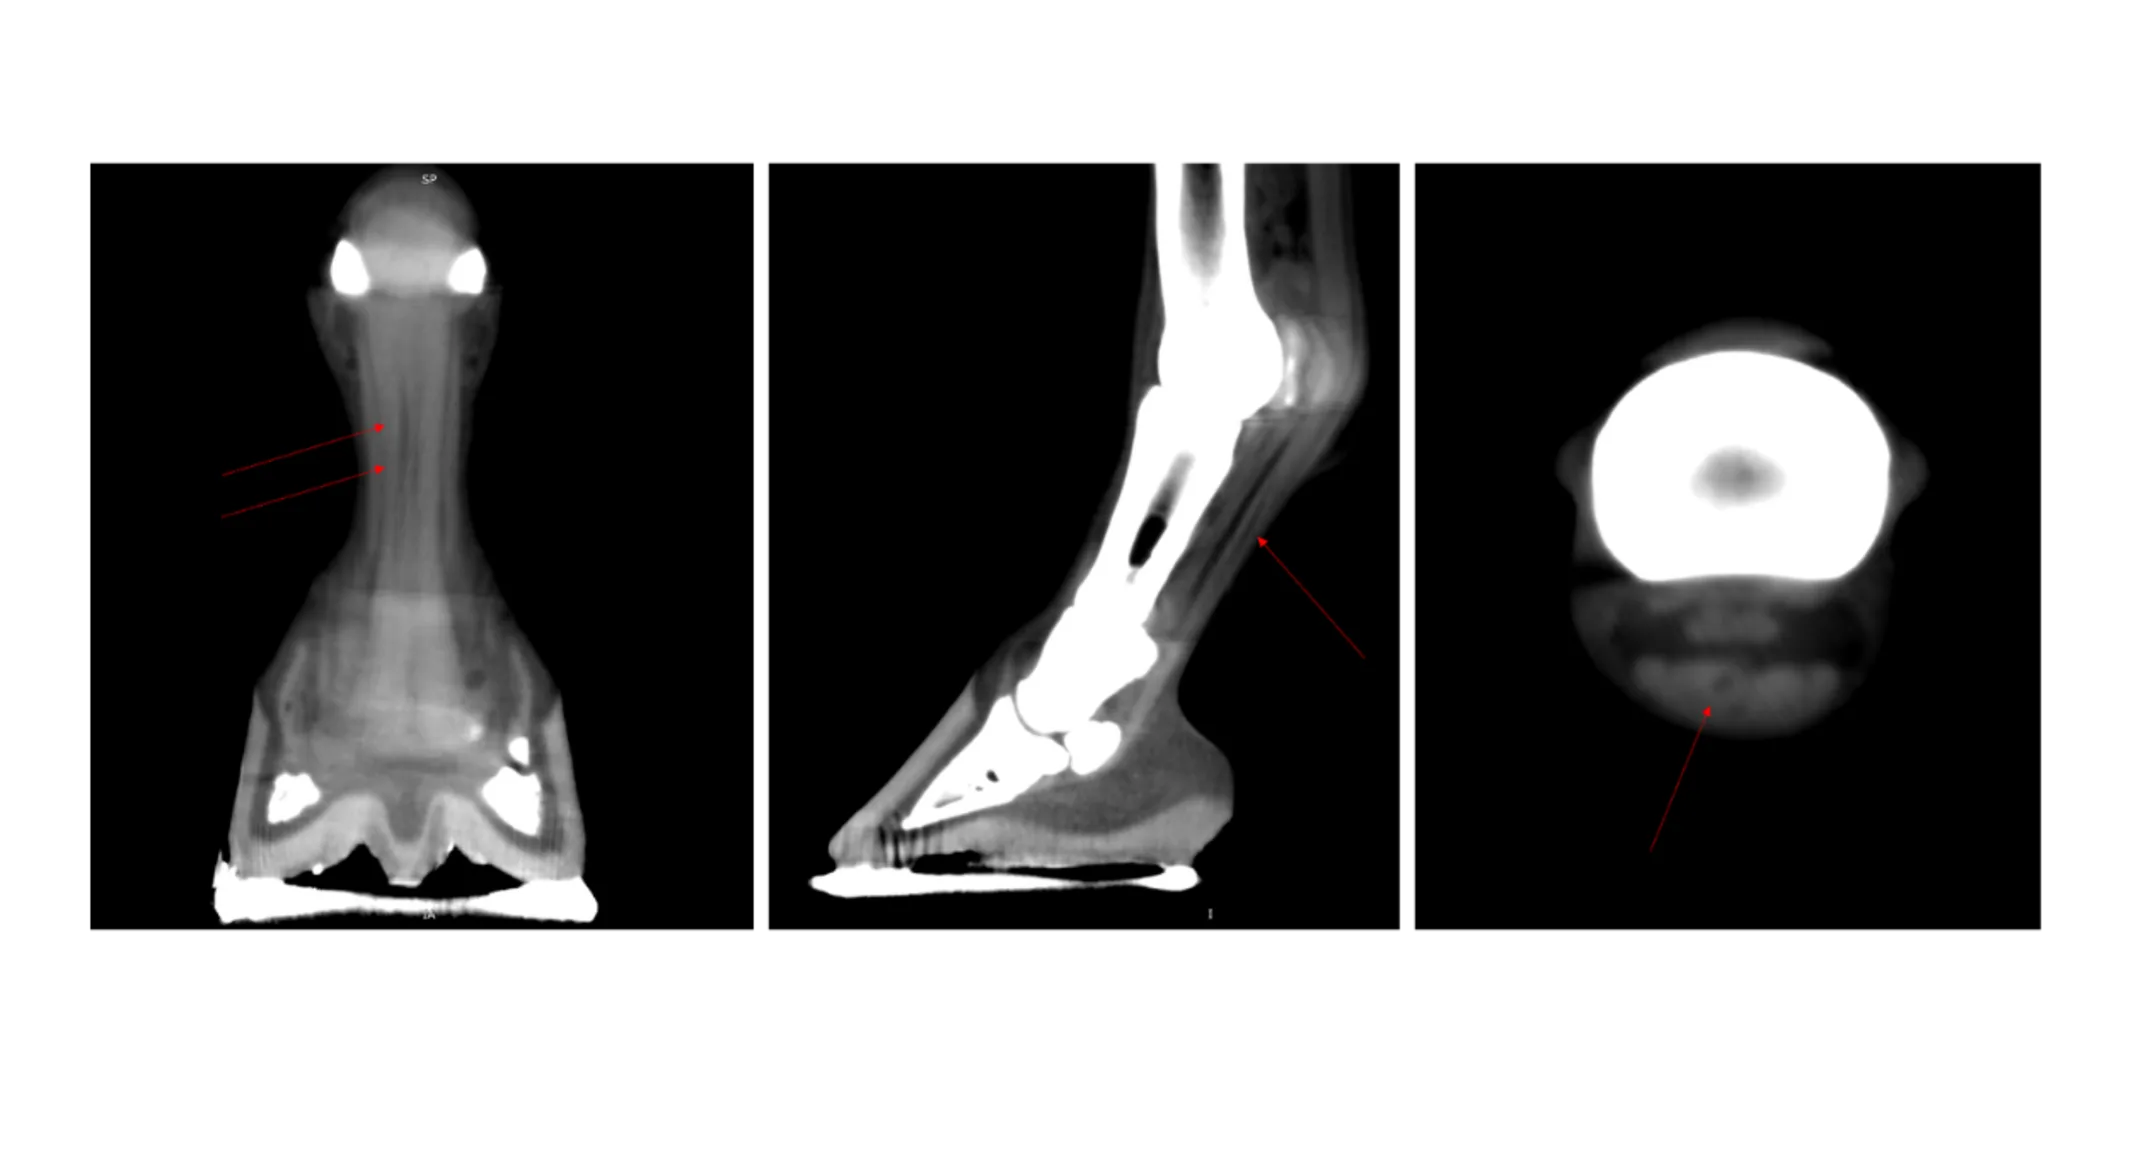

Case #3 – Distal Front Limb CT

History: 15-year-old Thoroughbred mare presenting for evaluation of a persistent LF lameness. The lameness resolves with an abaxial nerve block. The mare has a history of a deep digital flexor tendon tear diagnosed with a standing MRI 3 years prior.

Diagnosis: Progressive deep digital flexor tendon tears from mid-pastern to the distal aspect of the navicular bone.